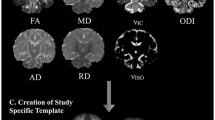

Image analysis

For all four imaging biomarkers (FA, MD, λ ax and λ rad), tract-averaged values were derived from eight major fasciculi segmented using probabilistic neighbourhood tractography (PNT) optimized for neonatal dMRI data (Bastin et al. 2010; Clayden et al. 2007; Anblagan et al. 2015). In summary after conversion from DICOM to NIfTI-1 format, the dMRI data were preprocessed using FSL tools (http://www.fmrib.ox.ac.uk/fsl) to extract the brain and eliminate bulk patient motion and eddy current-induced artifacts by registering the diffusion-weighted to the first T2-weighted EPI volume of each subject. Using DTIFIT, MD and FA volumes were generated for each subject. From the underlying white matter connectivity data, eight major white matter fasciculi thought to be involved in cognitive functioning were segmented: genu and splenium of corpus callosum, left and right cingulum cingulate gyrus (CCG), left and right corticospinal tracts (CST), and left and right inferior longitudinal fasciculi (ILF). As described in detail in the study by Anblagan et al. (2015), this involved using reference tracts created from a group of 20 term controls.